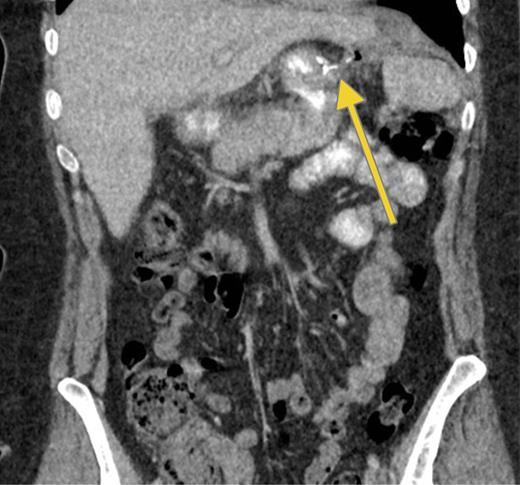

Three months later, patient presented with recurrent abdominal wall abscess. A GS demonstrated ongoing leak from the GCF (Fig. 2). On 8 September 2014, she underwent a laparoscopic fistulectomy. The fistula tract was transected and the gastric part of fistula excised. The spleen was involved in the inflammatory cavity, but splenectomy was eventually avoided. Since the gastric sleeve was healthy, it was decided not to resect the remaining stomach. No evidence of a fistula was detected on a GS performed at the 6-week postoperative check (Fig. 3).

Persistent leak detected with GS. The images clearly show persistence of the leak along with the fistula tract. One of the endoscopic clips previously positioned is also visible.